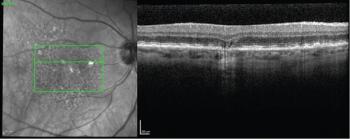

In an attempt to halt the progression of dry AMD and geographic atrophy, the use of high-resolution optical coherence tomography becomes pivotal.